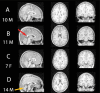

Forty years ago, alcohol was not commonly recognized as a teratogen, an agent that can disrupt the development of a fetus. Today, we understand that prenatal alcohol exposure induces a variety of adverse effects on physical, neurological, and behavioral development. Research supported by the National Institute on Alcohol Abuse and Alcoholism (NIAAA) has contributed to the identification of the range and prevalence of fetal alcohol spectrum disorders (FASD), as well as methods for prevention and treatment of FASD. The worldwide prevalence and high personal and societal costs of FASD speak to the importance of this research. This article briefly examines some of the ways that NIAAA has contributed to our understanding of FASD, the challenges that we still face, and how this research is translated into changes in public policy.